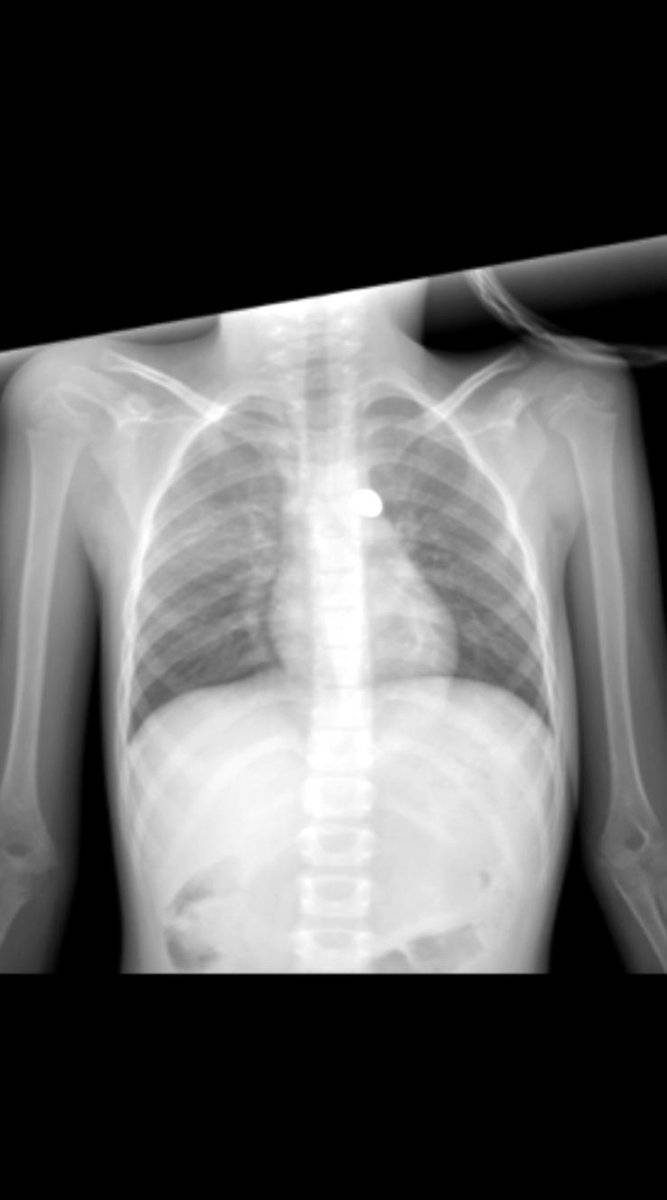

MERMİ ÇIKARILAMADI

İhbar üzerine bölgeye çok sayıda polis ve sağlık ekibi sevk edildi. 3 yaralı, ambulanslarla hastaneye kaldırıldı. Yağmur Demir, götürüldüğü özel hastanedeki ilk müdahalesinin ardından Çukurova Üniversitesi Tıp Fakültesi Balcalı Hastanesi’ne sevk edildi. Burada tedaviye alınan küçük Yağmur’un sırtındaki, omuriliğine yakın olduğu belirlenen mermi, riskli olduğu gerekçesiyle çıkarılamadı.